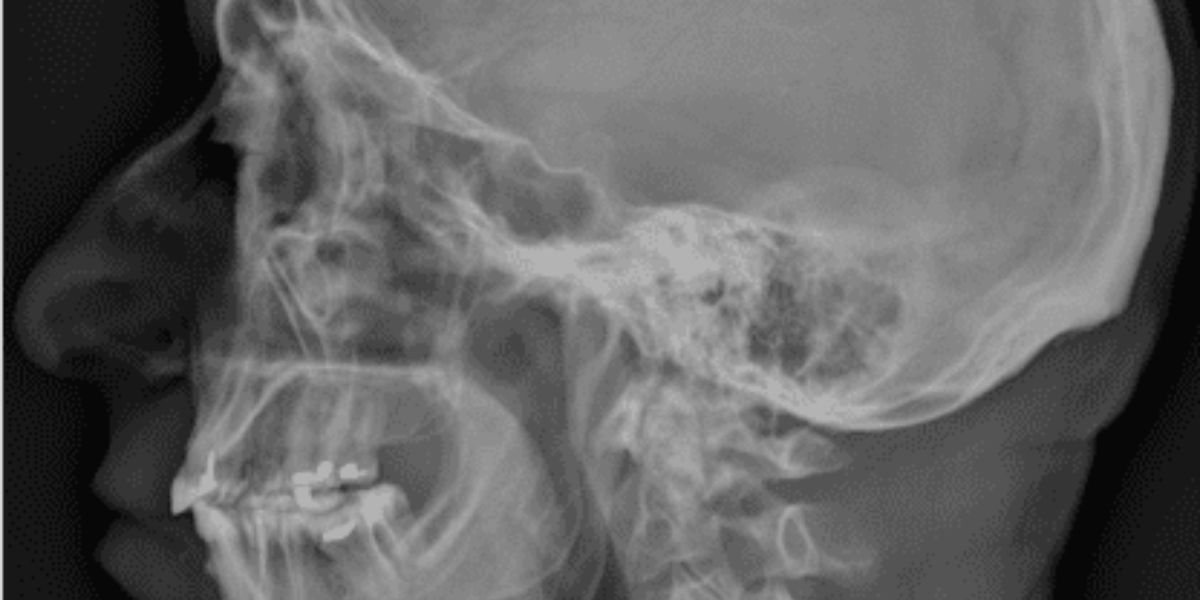

L’abbreviazione RX si riferisce alla radiografia, un metodo di imaging medico che utilizza radiazioni ionizzanti per creare immagini dettagliate delle strutture ossee e dei tessuti interni. L’RX Ossa Nasali si focalizza sulle ossa del naso, fornendo un’immagine chiara e nitida che consente di visualizzare eventuali alterazioni.

L’RX Ossa Nasali è un esame non invasivo che viene effettuato presso il Poliambulatorio S-Medical Group di Sora e si avvale di una quantità minima di radiazioni per ottenere immagini delle ossa nasali. Questo esame è particolarmente utile per individuare lesioni traumatiche, come fratture o dislocazioni, nonché per valutare deviazioni del setto nasale, sinusiti croniche o la presenza di polipi.

Cosa si Osserva con un RX Ossa Nasali?

L’RX Ossa Nasali permette di visualizzare chiaramente le ossa del naso e le loro eventuali anomalie strutturali. Questo esame risulta particolarmente efficace per:

• Identificare Fratture: L’RX evidenzia eventuali linee di frattura e scomposizioni ossee.

• Valutare il Setto Nasale: Consente di osservare deviazioni che potrebbero ostacolare la respirazione corretta.

• Diagnosticare Sinusiti: Rileva accumuli di liquidi o infiammazioni nei seni nasali.

• Individuare Polipi o Masse: Consente di osservare la presenza di eventuali formazioni anomale.